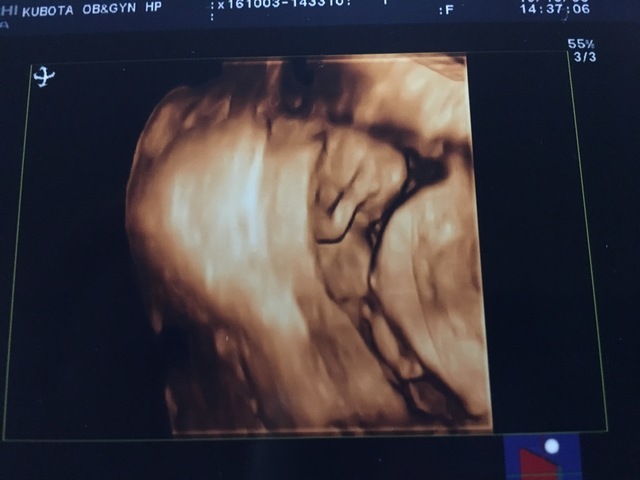

13週1日(13w1d・男の子)|ぽよぷに さん(27歳)

エコー写真撮影時のエピソード:

初めての4Dエコー。狭い子宮の中で、右手をあげているところがなんともたまらなくかわいい。生まれてからも右手をいつもあげているのかな?と想像がたくさん膨らみ、会える日が待ち遠しい気持ちでした。

つわりが辛い時だったけど、エコーを見て元気づけられたよ。この頃には、男の子確定のようなお言葉を頂きました!4Dエコーがこんなにハッキリ見えるとは思ってなく、ぜひおすすめします。